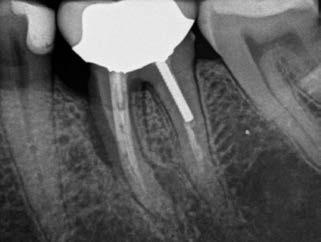

1. a–g. ábrák: A direkt pulpasapkázás lépései. Kiindulási bitewing-felvétel: A meglévő restaurátum közel helyezkedett el a pulpakamrához (a). Kiindulási periapicalis felvétel: Nincs periapicalis elváltozás fennállására utaló jel (b). A pulpaexpozíció (c). A vérzéscsillapítás céljából 20 másodpercen keresztül steril vattagombóccal történő kompressziót követően látható pulpaseb (d). A pulpasapkázás céljából behelyezett anyag, a széli részek tisztázása előtt készült felvétel (e). A röntgenárnyékot nem adó ideiglenes tömés behelyezése után készült felvétel (f). Az első ülés végén a röntgenárnyékot nem adó ideiglenes töméssel ellátott fogról készített röntgenfelvétel (g).

2. ábra: A hat hónapos kontroll alkalmával készített röntgenfelvételen vastag dentinhíd látható a pulpasapkázó anyag alatt.

3. ábra: A hároméves kontroll alkalmával készített röntgenfelvételen megfigyelhető a restaurátum pontos illeszkedése.

A diagnózisunk reverzibilis pulpitis volt. Periapicalis elváltozás jelenlétét nem vélelmeztük. A fogban lévő amalgámtömés eltávolítása során körülbelül egy 3 mm átmérőjű pulpaseb keletkezett a buccalis pulpaszarvnak megfelelően (1. a–g. ábrák) Mivel nem tapasztaltunk jelentős vérzést, és a diagnózisunk reverzibils pulpitis volt, ezért a direkt pulpasapkázás elvégzése mellett döntöttünk.

A kavitást 2,5%-os nátrium-hipoklorit oldattal fertőtlenítettük, majd sűrű konzisztenciájú kalcium-szilikát alapú anyagot (CeraPutty, Meta Biomed) készítettünk elő a direkt pulpasapkázás elvégzéséhez. Az első kezelés végén röntgenárnyékot nem adó ideiglenes töméssel (NexTemp LC, Meta Biomed) zártuk

az üreget annak érdekében, hogy a direkt pulpasapkázásra használt anyag megfelelő pozícióját radiológiailag ellenőrizni tudjuk. A második ülés során kompozit tömőanyagból (Ezfil, Meta Biomed) direkt adhezív restaurátumot készítettünk.

A kezelést követően a beteg tünetmentes volt. A kérdéses fog a kontrollvizsgálatok során végzett szenzibilitástesztekre fiziológiás reakciókat adott. A hat hónapos kontroll alkalmával készített röntgenfelvételen a sérülésnek megfelelően széles dentinhidat észleltünk (2. ábra). A restaurátum a hároméves kontroll során is megfelelőnek bizonyult (3. ábra)